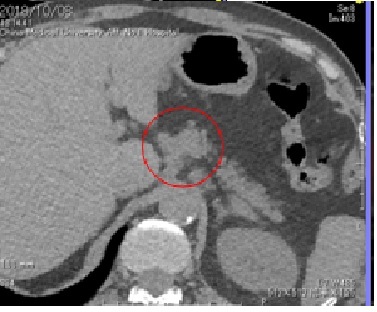

2018年10月复查,PET CT确诊肺腺癌3A期术后多发转移。但因胃小弯侧及腹膜后膜主动脉旁多发淋巴结影(最大SUV10.2较2017-09-21,病灶增多,代谢增高),紧邻胃壁,很难接受国内传统放疗,极易引发胃穿孔,同时多发转移无法手术,仅考虑化疗,但不排除化疗药物出现耐药性后病情恶化。

A: 1-4。从胃上部大弯侧淋巴节到腹腔动脉干右侧的淋巴节可见不规则的如同姜根状的连续肿大淋巴结,该部位FDG呈现集聚。淋巴节有转移巢的可能性。

针对A病灶靶区,与胃部临近,建议通过拥有动态追踪功能的最新一代M6机型(全日本仅3台)高精准放射线进行治疗,治疗前可注入凝胶进行隔离,如果因胃部蠕动而万一发生凝胶无法固定的情况,M6机型也可在注意胃部危险器官的同时进行高剂量的精准照射(只有M6机型才能做到)。